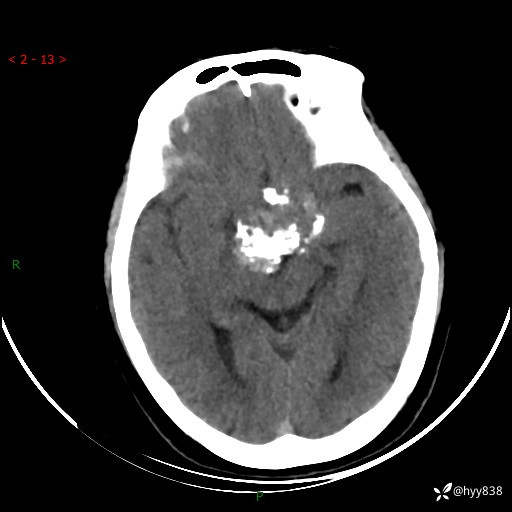

颅脑CT平扫

老年女性,视力下降3年。鞍区钙化性肿块,鉴别诊断有哪些---(有结果)

简要病史:患者3年前无明显诱因左眼出现视力下降,出现视物模糊,无头痛,无头晕,无恶心、呕吐,无意识障碍,无肢体麻木及抽搐,无心慌、胸闷,无腹痛、腹胀等不适,无旋地转感。个月前右眼视力下降,患者视物模糊逐渐下降,自诉看东西有雾感。在当地医院眼科就诊,症状无好转,行头部MR提示:鞍区肿物。现患者为求诊治来我科就诊,在当地市中医医院行头部CT:提示鞍区占位。患者现求进一步诊治来我院就诊,门诊以“鞍区肿物”收入我科。 患病以来,患者精神、饮食、睡眠尚欠佳,大小便如常,体力体重无明显变化。

临床诊断:鞍区肿物